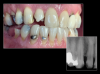

Fig 4. Left: This intraoral photograph taken with only a smartphone shows image distortion and poor color rendering. Right: This intraoral photograph was taken with a DSLR camera with an external flash and is much higher quality.

Figure 4